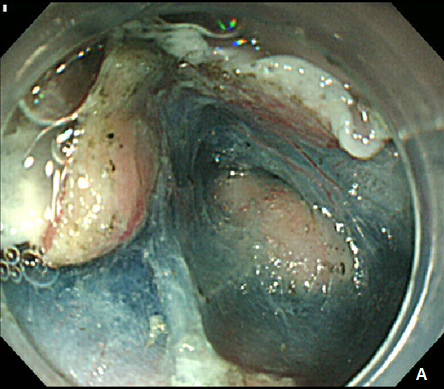

Figure 1 Esophageal subepithelial tumor (SET).

(A) An esophagogstroduodenoscopy (EGD) showed a large (4.0 cm) SET at upper to mid esophagus. (B) An endoscopic ultrasonography showed a large hypoeshoic mass originated from muscularis propria layer.